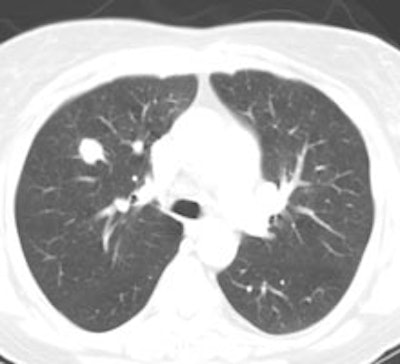

Example: The CT scan in this patient demonstrated a small nodule in the left upper lobe (black arrow). PET-FDG images demonstrate very intense accumulation of the tracer within the lesion (white arrow), which was a non-small cell lung cancer. (Case courtesy of H. Page McAdams MD, Department of Radiology, Duke University Medical Center) |